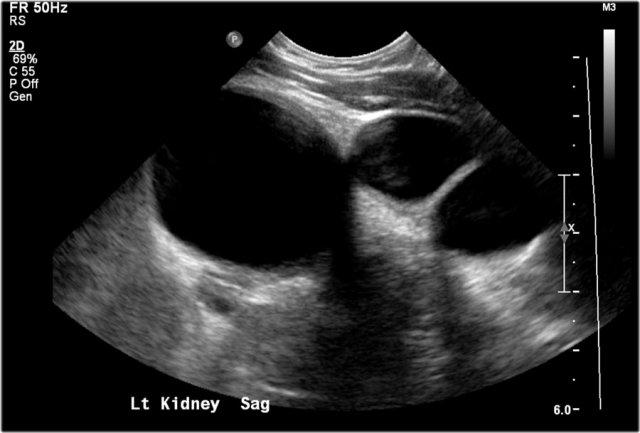

Đây là hình ảnh siêu âm của một bé trai 5 tháng tuổi được phát hiện trước sinh có hệ thống đài bể thận giãn và không thấy niệu quản, phù hợp với hẹp khúc nối bể thận – niệu quản.

Trên mặt cắt dọc, hệ thống đài bể thận giãn được hiển thị rõ ràng.